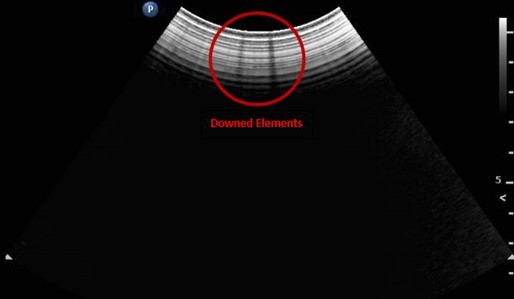

This is visible in the photo below.

Inside your cable are hundreds of tightly bound wires. Each wire represents an element which together make up the entirety of your ultrasound image. If one or more of those wires is damaged, it can lead to black lines in your image referred to as dead elements. What this means is that the wire is now unable to transmit the signal from the probe head to the machine it is connected to and thus does not appear on your image.